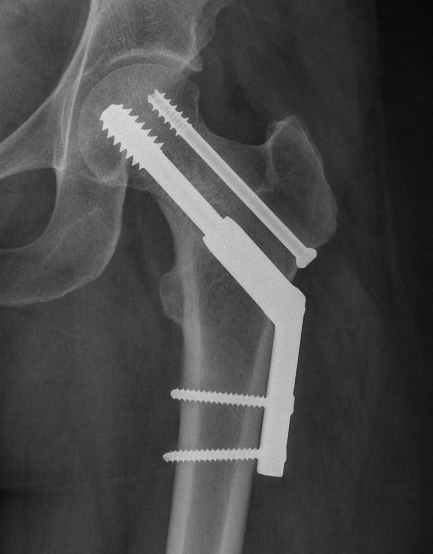

Coxa vara / coxa valgus

? FAI

Femoral neck fracture on right in patient with coxa vara

Surgery

Options

- cannulated screws

- DHS + derotation screw

- +/- minus open reduction